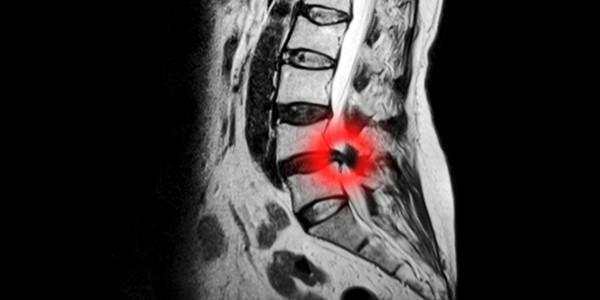

What is a Herniated Disc?

An intervertebral disc is the spongy shock absorbing tissue between the bones in your spine.

What is commonly known as a 'slipped disc' is more accurately described as a herniated or prolapsed disc, when the central tissue for the disc (the nucleus) breaks through the outer casing of the disc (the annulus) causing herniation.